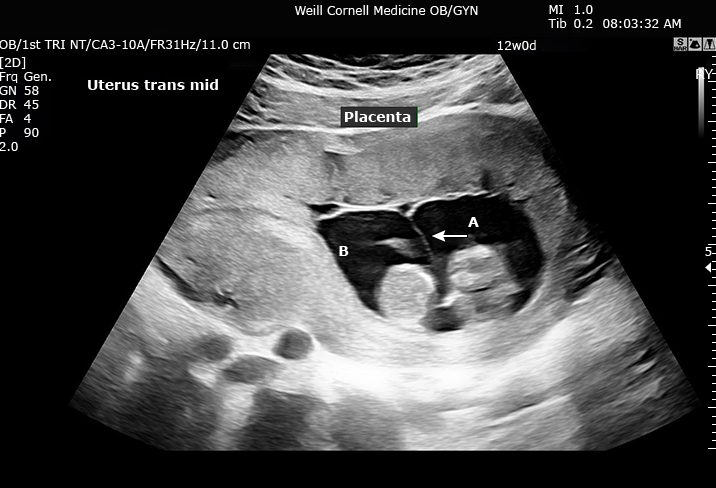

Signo de lambda que tipo de embarazo múltiple sugiere

Dichorionic diamniotic

Signo de la T que tipo de embarazo múltiple sugiere

Monochorionic diamniotic